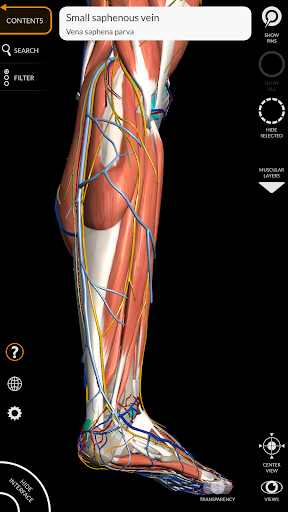

يتيح لك "Anatomy 3D Atlas" دراسة التشريح البشري بطريقة سهلة وتفاعلية.

من خلال واجهة بسيطة وبديهية، من الممكن ملاحظة كل بنية تشريحية من أي زاوية.

تتميز النماذج التشريحية ثلاثية الأبعاد بتفاصيل خاصة ودقة تصل إلى 4K.

يسهل التقسيم حسب المناطق والمناظر المحددة مسبقًا مراقبة ودراسة الأجزاء الفردية أو مجموعات الأنظمة والعلاقات بين الأعضاء المختلفة.

• الجهاز العضلي الهيكلي

• تدوير وتكبير كل نموذج في مساحة ثلاثية الأبعاد

• خيار إخفاء أو عزل نموذج واحد أو نماذج متعددة مختارة

• فلترة لإخفاء أو عرض كل نظام

• وظيفة البحث للعثور بسهولة على كل جزء تشريحي

• تصور العضلات من خلال مستويات الطبقات من الطبقات السطحية إلى الأعمق

• من خلال تحديد نموذج أو دبوس، يظهر المصطلح التشريحي ذي الصلة